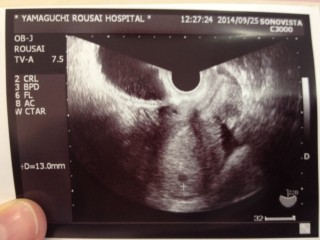

先週ほんの小さな黒い丸が見えましたが、今週また確認すると、真ん中らへんに0.5cmと0.6cmの二つの胎のうが確認されて、二卵性双生児という事がわかりました!ビックリです!!初産で、不安もいっぱいですが楽しみです(*^^*)

最終月経からしたら7w0dのはず! でも、生理不順で排卵ずれたりで、先生には5wぐらいの大きさ。 正常妊娠おめでとう!って言ってもらえました

次は2週間後にまた受診(^ω^)

心拍確認できますように!